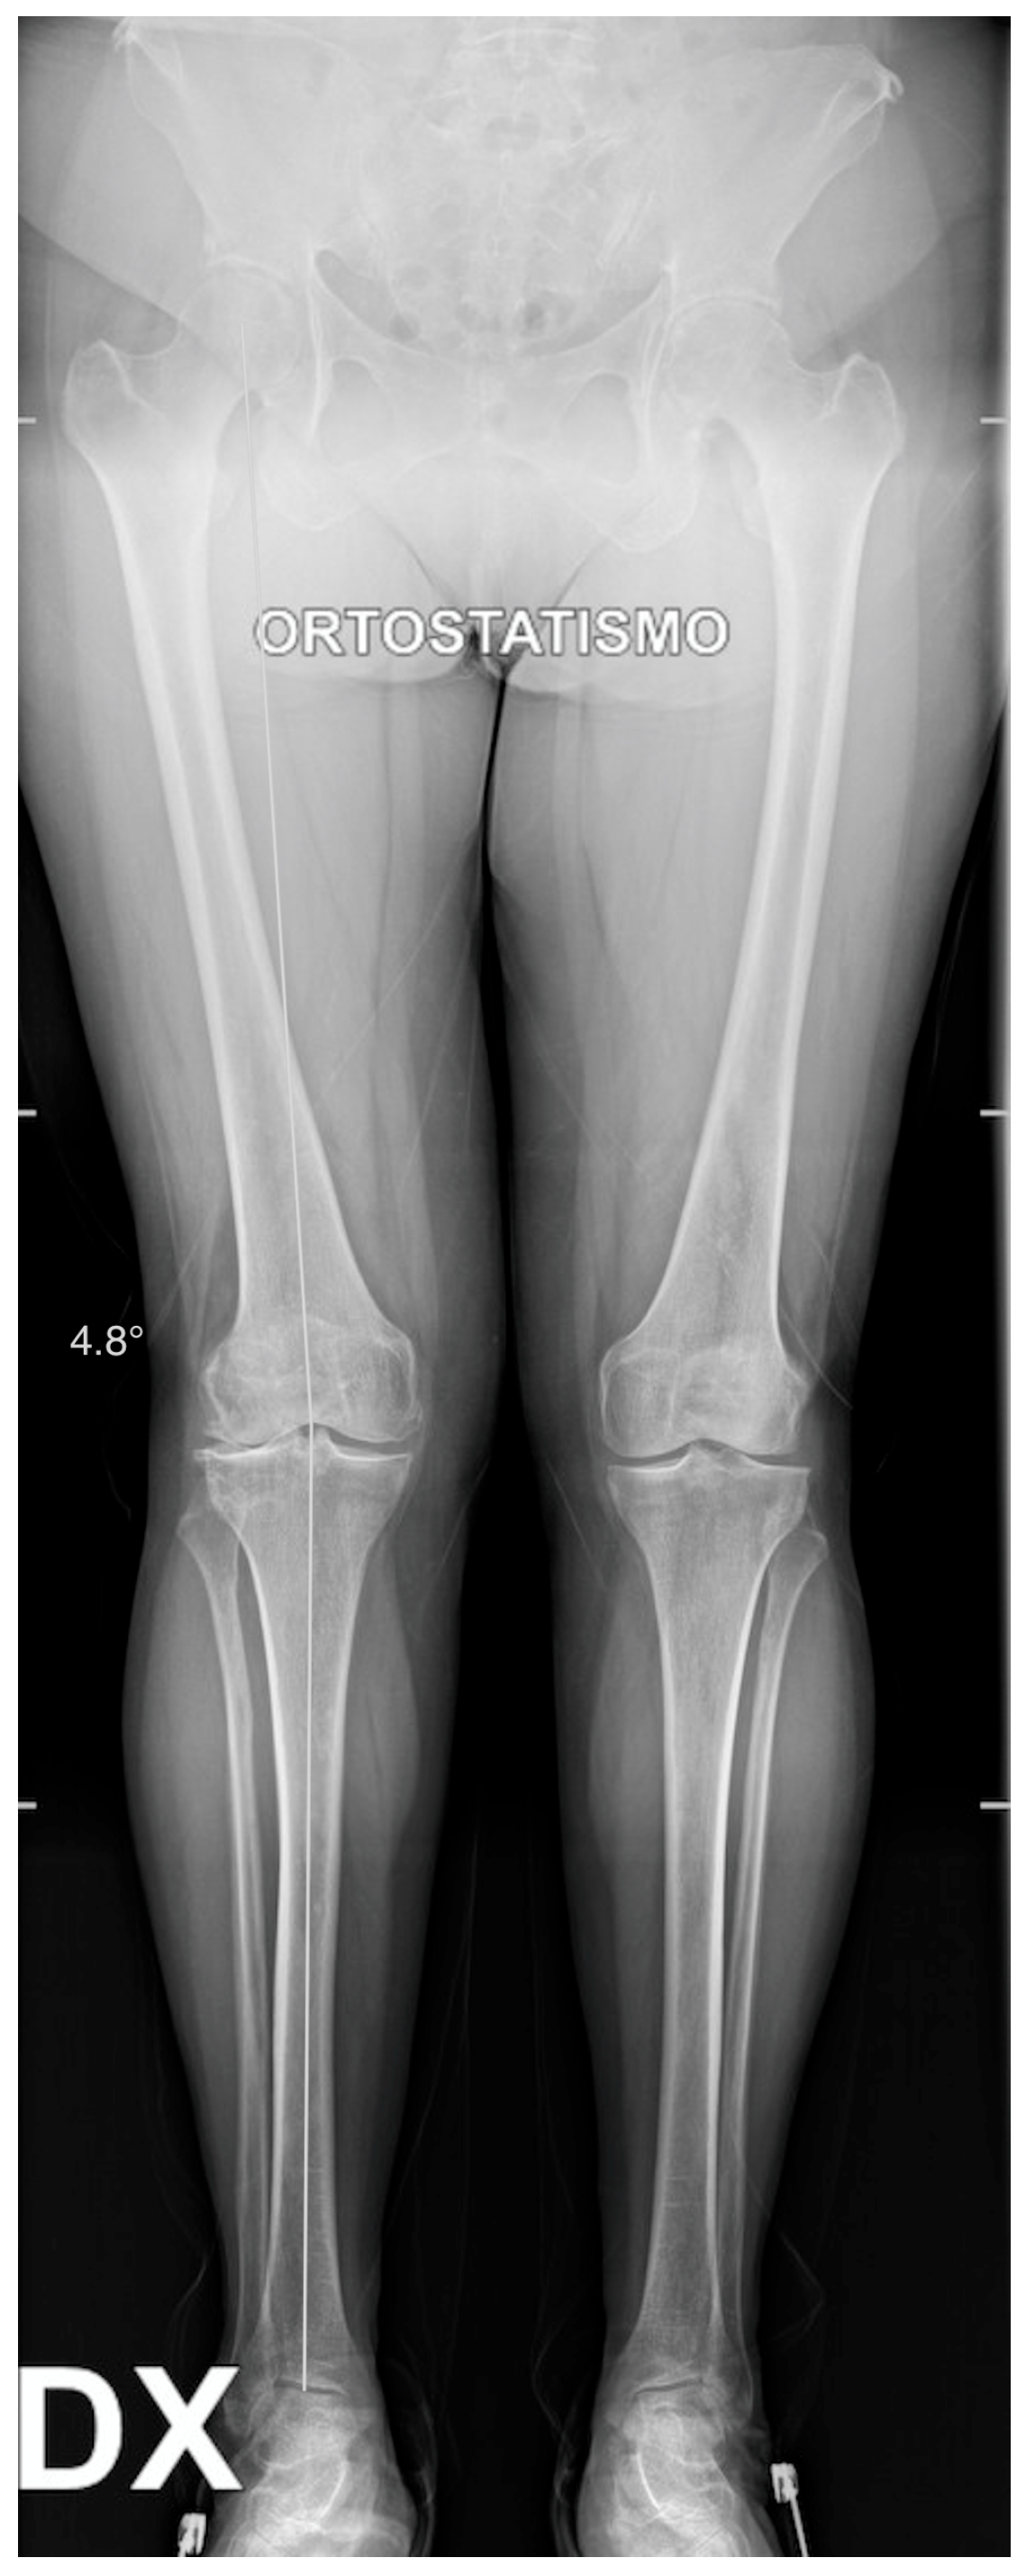

X-rays were obtained. The X-rays showed a valgus knee (4.8 degrees of mechanical axis and 11 degrees of anatomical one) (Figure 1). The antero-posterior X-rays showed lateral osteoarthritis. Based on Kellgren–Lawrence, there was evidence of grade IV on the lateral compartment and a grade II–III on the patella-femoral joint and on the femoro-tibial compartment (Figure 2).

Figure 1.

Long standing X-ray. Valgus knee: 4.8 degrees of valgus.